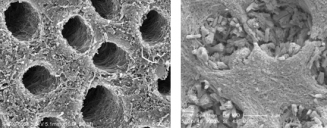

此研究透過掃瞄式電子顯微鏡檢查,發現塗上聚多巴胺的牙齒有再礦化現象,在琺瑯質及象牙質皆可找到新的礦物晶體。不但可在象牙質表面看到礦物晶體,更可在象牙質內的微細管道看到。至於沒有覆蓋聚多巴胺的牙齒,則只有琺瑯質有再礦化。

研究員們總結出聚多巴胺是不會阻礙琺瑯質再礦化,及能修改牙齒表面來刺激象牙質再礦化。他們認為聚多巴胺能結合象牙質蛋白質及膠原,那裏便能提供形核位置,吸引鈣與磷酸鹽結構及使礦物晶生長,並特別生長在象牙質微細管道內。

研究的作者們解釋四份三人口有敏感牙齒的問題是因為接連牙齒神經線的象牙質微細管道外露,當聚多巴胺的外層再加上鈣和磷酸鹽似能填補所有象牙質的微細管道,他們稱對此敏感牙齒方法為「潛在醫療技術」。兼且此方法亦可代表著一個「簡單的、普遍的技術」去為琺瑯質及象牙質修補礦物。不過,作者們提出一點需要注意的,就是用聚多巴胺作臨床實驗研究時,可能使人體產生出有害的效應和影響。